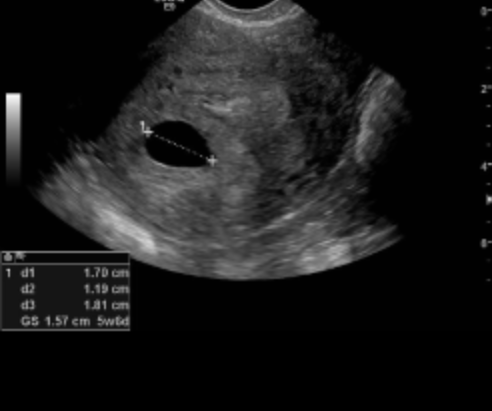

My scan revealed a five week and six day gestational sac with a small yolk sac inside but no fetal pole. Measuring nearly two weeks off my actual dates they suggested I possibly ovulated late and to come back in a week to see if there was growth and a fetal pole then. I went back and in exactly a week the sac had grown to six weeks and the yolk sac still present. The diagnostic was a Blighted Ovum at that point, I had never heard of this before and spent time wrapping my head around such a thing.

Coming up to week ten/eleven of my pregnancy I began to bleed and this time it was red PV bleeding and it wasnt slowing, accompanied by cramping my partner encouraged me to go to the emergency room as this was hitting both of us pretty hard we didn’t want to sit and wait anymore. They saw me straight away and did a spec exam and HCG blood test. I had a closed cervixs and my bloods showed my hcg had dropped only slightly so again with a smile on the doctors face she said this was a threatened miscarriage and sent me for a scan, the truth was there in the scan a blighted ovum no viable pregnancy and the gestational sac was still growing it was showing to have grown to seven weeks gestation.

I went to the emergency room and luckily I had the same doctor who had seen my at the early pregnancy unit and the day prior when I went to emergency. He was so respectful and really moved things along for me, he showed compassion it was a light in a time of darkness for me. I had another scan to confirm the blighted ovum, even now it nearly eleven weeks along in my pregnancy my scan showed a gestational sac of seven weeks and no viable life inside even the yolk sac had disappeared. I requested a DNC (dilatation and curettage) after another confirmation scan and blood checks by the head gynecologist/doctor I got approved to go on the emergency wait list and made Nil by mouth to wait for a surgery I was possibly having that day.